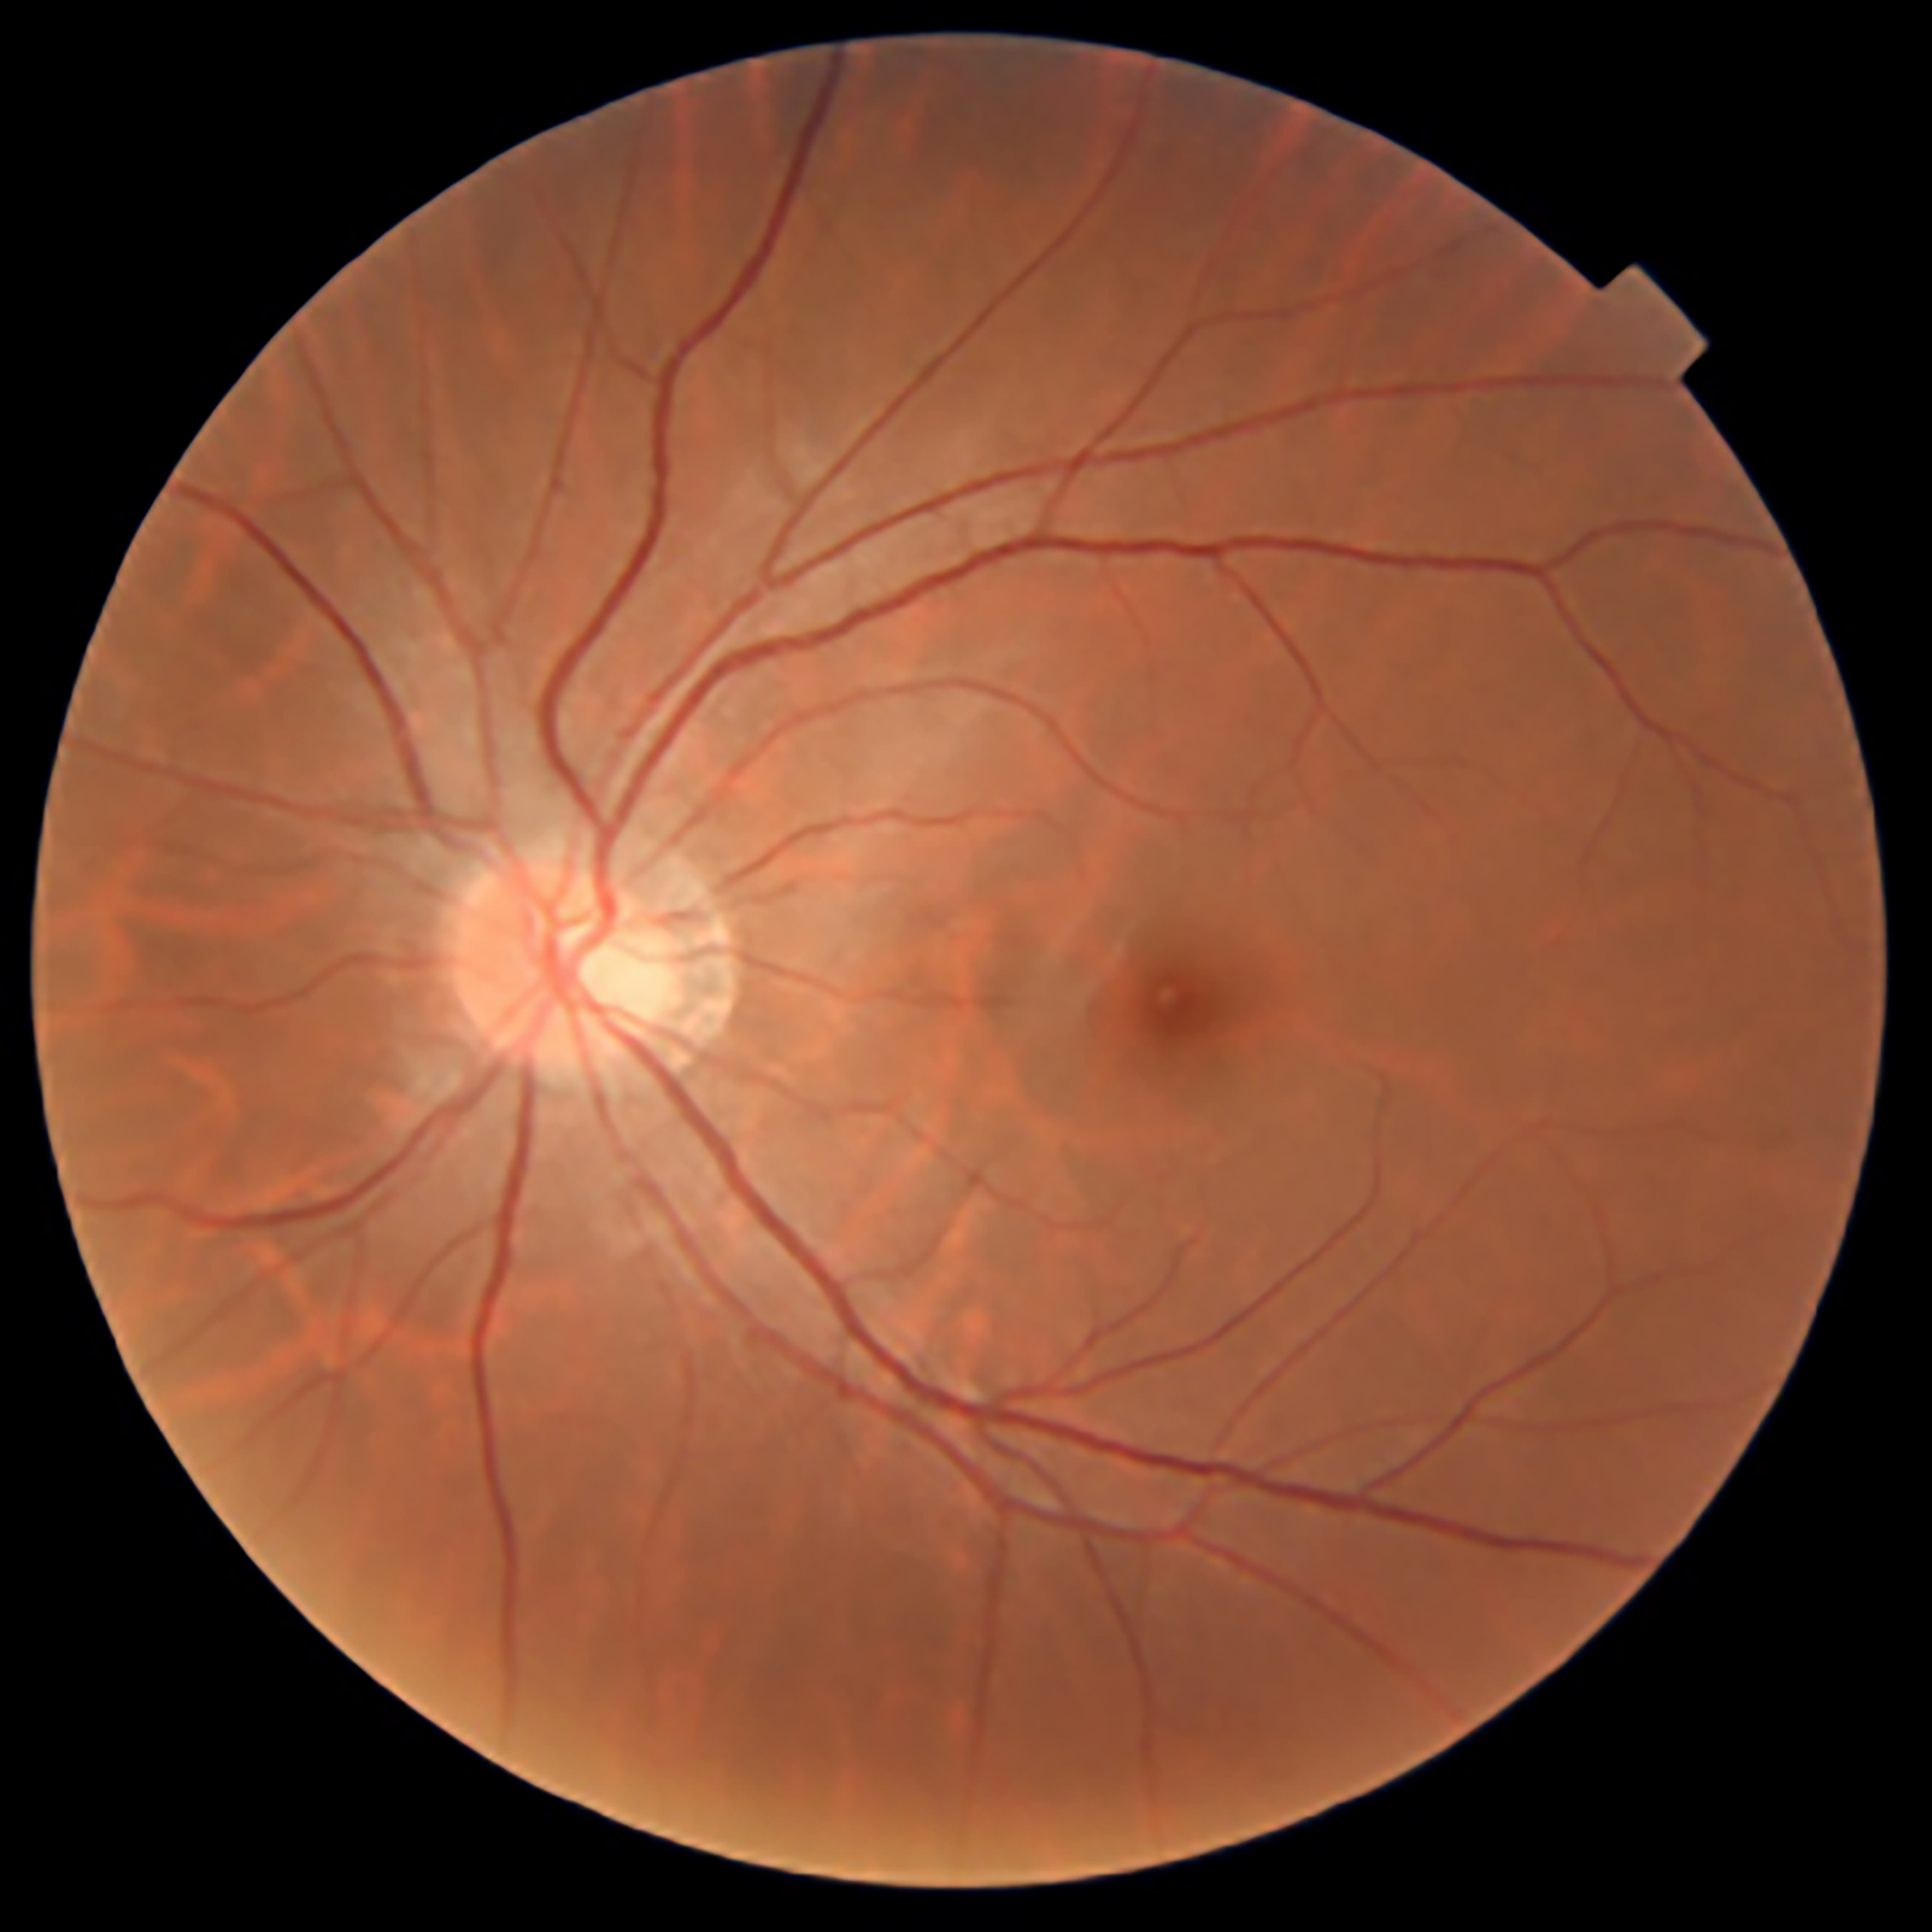

Figure 1: A retinal photograph of a healthy left eye. The fine blood vessels emerge from the yellow optic nerve, which connects the retina to the brain.

These nerve fibres converge to form the optic nerve, which also gives rise to the network of blood vessels that nourish the retina

(see Figure 1).